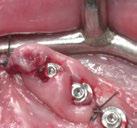

Ejecución técnica quirúrgica mediante férula guiada Bajo anestesia infiltrativa realizamos extracciones atraumáticas de todas las piezas a excepción de los dientes que actúan como anclaje o pilares para la fijación de la férula quirúrgica (Figuras 20 y 21). Seguidamente insertamos la férula comprobando una buena adaptabilidad y estabilidad

(Figuras 22 y 23). Se realiza fresado transgingival mínimamente invasivo y guiado hasta la inserción de los implantes, siguiendo el protocolo preestablecido e indicado (Figuras 24 a 26).

Durante la colocación de los implantes comprobamos una inserción con torque superior a 35 N/cm2

Retiramos la férula y comprobamos una correcta estabilidad primaria mediante mediación de valores

ISQ favorables en la mayoría de los implantes. Seguidamente se extraen los dientes remanentes que han actuado de medio retentivo para la férula quirúrgica.

Dentro de la fase quirúrgica propiamente dicha, una vez terminada la inserción de los implantes y

comprobada su estabilidad primaria, colocamos pilares transepiteliales

Multiplus para registrar una impresión digital mediante escaneado sobre ellos (Figuras 27 a 29)